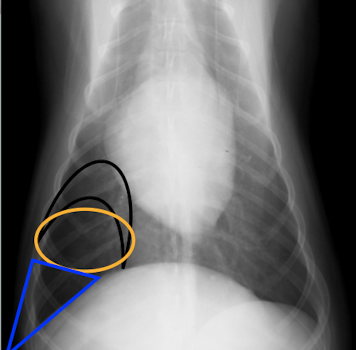

Label the image

intra-capsular soft tissue swelling

osteophytes

enthesophytes

subchondral erosions

intra-articular calcified bodies

subchondral sclerosis

subchondral cysts

joint space narrowing